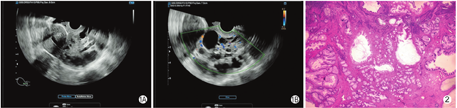

患者女,44岁,阴道间断出血1月余。孕3产2。查体:宫颈后唇正常形态消失,触之出血,宫颈管及阴道后穹隆见白色黏液。宫颈液基薄层细胞学检查(thin-prep cytology test,TCT):阴性。MRI检查:宫颈多发纳氏囊肿、宫颈内膜增生伴炎性改变可能。超声检查显示:宫颈形态失常,宫颈与阴道前、后穹隆存在分界,宫颈内口显示不清,宫颈内见囊实性回声团,大小84 mm×63 mm,边缘尚清,实性部分呈稍高回声,囊性部分大小不等,形态不规则。彩色多普勒血流成像示:包块边缘及内部可测及少许短棒状彩色血流信号,阻力指数0.56(图1)。患者后行手术,术后病理:宫颈及颈管内见大小不等腺体成分,浸润性生长,腺细胞有异型,间质炎细胞浸润(图2),符合宫颈胃型腺癌(gastric type adenocarcinoma of the uterine cervix,GAS),侵及宫颈基质全层,累及宫颈管及子宫体下段。免疫组化:ER(-),PR(-),p16(局灶+),CK7(+),CK20(-),CDX-2(-),Pax-8(+),p53(散在+),CEA(-),MUC-6(部分+),Ki-67(60%+)。特殊染色:AB-PAS(部分+)。本研究经医院伦理委员会审批通过(广东省妇幼保健院医伦第[202201107]号)。

本例患者宫颈体积明显增大,其内部满布多发大小不一囊性回声,结合病理,囊性回声形成的病理基础是腺体囊性扩张,这是腺癌独有的特点,鳞癌通常表现为低回声肿物。Hino等[5]及Park等[6]基于MRI的研究认为GAS多表现为宫颈上段或累及宫颈全程的肿块,呈浸润性生长,肿块内部常可见到多发囊肿。本例患者声像图特点与之相符。与之容易混淆的病变是宫颈纳氏囊肿,后者通常局限于宫颈管,而GAS肿块内囊肿数量更多、分布更广泛,并且伴有宫颈体积增大。此外,本例患者肿块84 mm×63 mm,已超过40 mm,同时声像图显示宫颈内口结构消失,且宫颈与阴道前、后穹隆存在分界,提示肿瘤已浸及宫体下段而未侵犯阴道,这对宫颈癌分期有重要提示意义,提示临床分期至少为ⅡB期。值得注意的是,本例患者TCT结果为阴性,推测是因为病变呈内生性浸润生长,因此宫颈表面的细胞异型性不明显。对于无HPV感染,同时TCT阴性的女性,更应重视影像学检查,避免宫颈癌的漏诊。